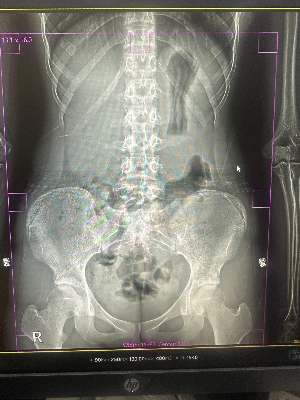

그렇다면 우리 장 속에 있는 가스는 어떻게 보일까요? 맞습니다. 아주 짙고 까만 풍선처럼 동글동글하게 보입니다. 그럼 대변은요? 대변은 음식물 찌꺼기와 수분, 가스가 엉켜있는 형태이기 때문에 엑스레이 사진상에서는 몽글몽글하고 얼룩덜룩한 '회백색의 자갈밭'이나 '모자이크'처럼 보입니다.

아까 그 20대 환자분의 사진에는, 오른쪽 아랫배부터 시작해서 대장을 따라 뱃속 전체에 까만 가스 풍선과 얼룩덜룩한 회백색 자갈밭이 빈틈없이 꽉 들어차 있었던 겁니다. 장이 꽉 막혀서 팽창해 있으니, 배가 찢어질 듯 아플 수밖에 없었죠!